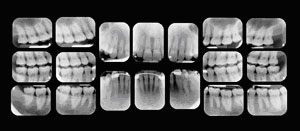

Regular checkups include a thorough cleaning and polishing by one of our professional hygienists and an oral exam by the doctor. During the oral exam, the doctor checks the health of your mouth, teeth, gums, cheeks, and tongue. At each visit, the doctor also checks old fillings and restorations because constant pressure from chewing, grinding, or clenching can cause them to wear away, chip, or crack. Your First VisitThere is nothing we enjoy more than welcoming new patients to our practice. Each new patient comes to us with their own unique dental history, goals for their dental health and desires for how they want to be treated. We respect your uniqueness and will spend time getting to know you. We will perform a comprehensive examination and most likely take a series of digital x-rays. We are proud to offer the latest in digital technology which greatly reduces exposure to radiation. We will discuss our findings together and develop the best course of treatment for you. Consultation After the doctor has evaluated your records, we discuss any follow-up treatment with you in detail, including the investment for your particular case. Regular Appointments Regular checkup appointments typically take 40 to 60 minutes. Patients are seen by appointment only. We make every effort to be on time for our patients and ask that you extend the same courtesy to us. If you cannot keep an appointment, please notify us immediately. ![]() Payment & Office Protocols Financial Investment We promise to always keep you informed about the cost of services. We will discuss fees and payment options prior to starting treatment. Fees In an effort to keep fees down while maintaining the highest level of professional care, we have established these financial protocols: